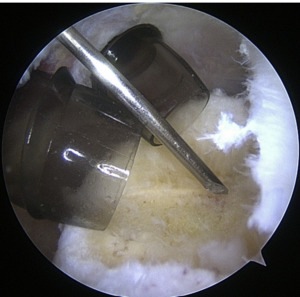

Setup

The coracoid, acromioclavicular joint, clavicle, and acromion are all marked on the skin. If subacromial work is going to be performed, the subacromial bursa may be infiltrated with up to 30 cm3 of a mixture of 0.25% bupivacaine and epinephrine. A standard posterior portal is the typical site of access to the subacromial area and glenohumeral joint. The typical placement of this opening is 2 centimeters medial and 2 centimeters distal to the posterolateral border of the acromion. Palpating the soft tissues of the posterior glenohumeral joint is a common way to confirm the proper position. An anterior portal develops after the joint has been inserted. Figure 4 shows that the surgeon has the option of employing a spinal needle to perform it from the outside in or an inside out approach, depending on his or her choice. The anterosuperior portal is located just off the outside edge of the acromion. You may find the anteroinferior portal directly on the side of the coracoid. One centimeter below the anteroinferior portal is the 5 o’clock portal, which is defined as passing through the subscapularis tendon. Scientists say this entry point is the most common and least invasive as it mimics neurovascular systems. Any anterior portal may be used to conduct basic shoulder arthroscopy. Figure 5 shows the setup of both anterior portals for biceps tenodesis, subscapularis repairs, and labral repairs. For posterior labral repairs, spinal needle localization allows for the creation of an auxiliary posterolateral portal situated immediately distal to the posterolateral limit of the acromion. Anterior positioning of the Wilmington portal, one centimeter laterally to the posterolateral margin of the acromion, is recommended for superior labral repairs. The posterolateral and Wilmington portals are types of trans-rotator cuff tendon access points. Cannulas with the smallest diameters necessary should be used.25

The subacromial region may be accessed via the posterior portal if needed after any intra-articular procedures are finished. Spinal needle localization allows for the creation of a lateral portal, typically 2 cm laterally to the acromion’s lateral border and aligned with the clavicle’s posterior border (Figure 6). For any subacromial surgery, pre-positioned anterior portals may be used (Figure 7). An extra Neviaser portal may be made underneath the spinal needle localization, precisely below the acromioclavicular joint, if that becomes essential. This may be useful for a variety of suture procedures, including those involving the superior labrum, the rotator cuff, and the decompression of the suprascapular nerve (Figure 8).25